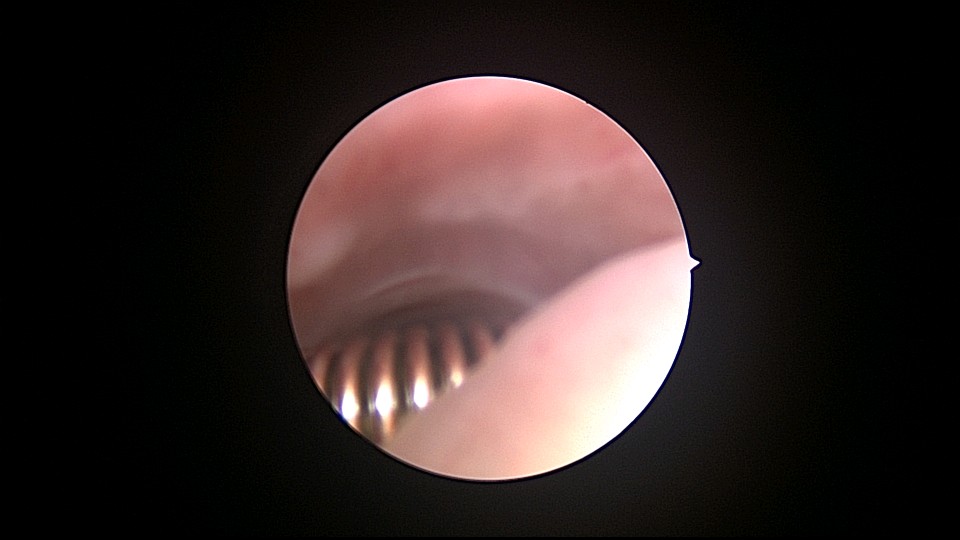

患者56岁,G4P1,顺产1次。1990、1991、1992年三次安环,均自然脱落,1993年第4次安环至今,共31年。现绝经4年,外院取环失败。患者阴道、宫颈、子宫萎缩,宫颈外口无法夹持,探针、中弯钳均无法打开宫颈外口,一筹莫展多时。最后用缝线缝住宫颈11点位及1点位,牵拉宫颈,尖刀片十字切开宫颈外口,B超监护下宫腔镜艰难进入宫颈管,见宫颈管封闭粘连,宫颈内口左侧粘膜下肌瘤遮挡视野。多次努力,镜子成功进入宫腔,见O型环两侧与子宫肌壁嵌顿,异物钳牵拉几次失败,用取环钩钩取,多次尝试终于成功钩住环,牵拉到宫颈外口,用中弯钳取出节育环,环变形,宫壁见节育环割裂痕迹,宫腔少许积血,无其他异常。